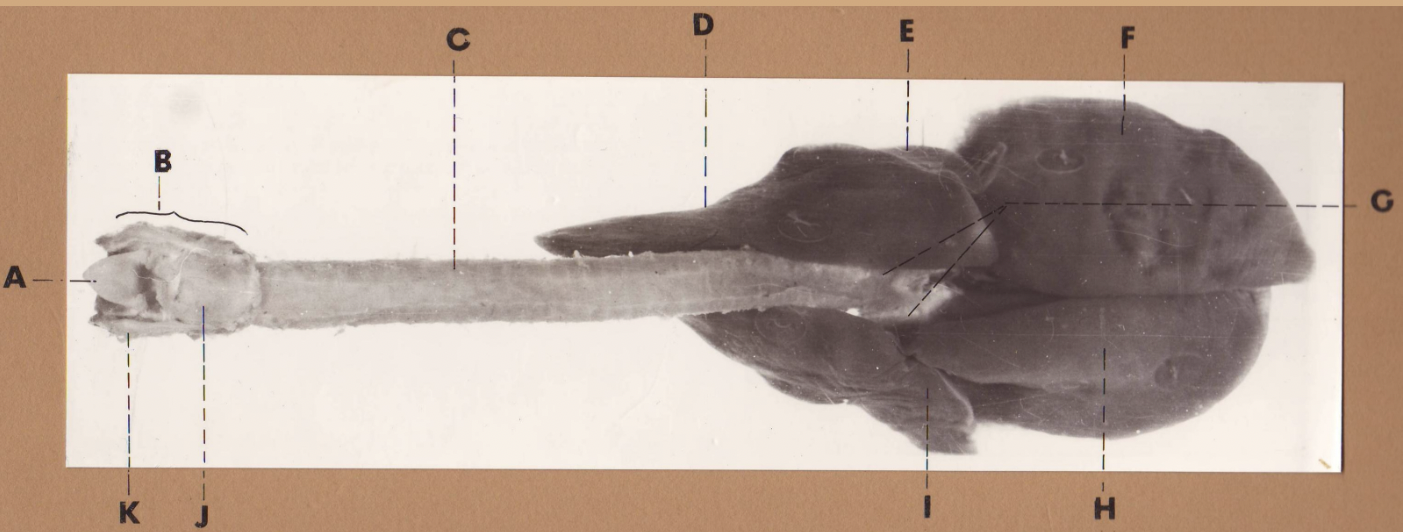

A

(cat larynx/trachea/lungs, dorsal)

epiglottis

B

(cat larynx/trachea/lungs, dorsal)

larynx

C

(cat larynx/trachea/lungs, dorsal)

trachea

D

(cat larynx/trachea/lungs, dorsal)

R cranial lobe

E

(cat larynx/trachea/lungs, dorsal)

middle lobe

F

(cat larynx/trachea/lungs, dorsal)

R caudal lobe

G

(cat larynx/trachea/lungs, dorsal)

primary bronchi

H

(cat larynx/trachea/lungs, dorsal)

L caudal lobe

I

(cat larynx/trachea/lungs, dorsal)

L cranial lobe

J

(cat larynx/trachea/lungs, dorsal)

cricoarytenoideus dorsalis m

K

(cat larynx/trachea/lungs, dorsal)

thyroid